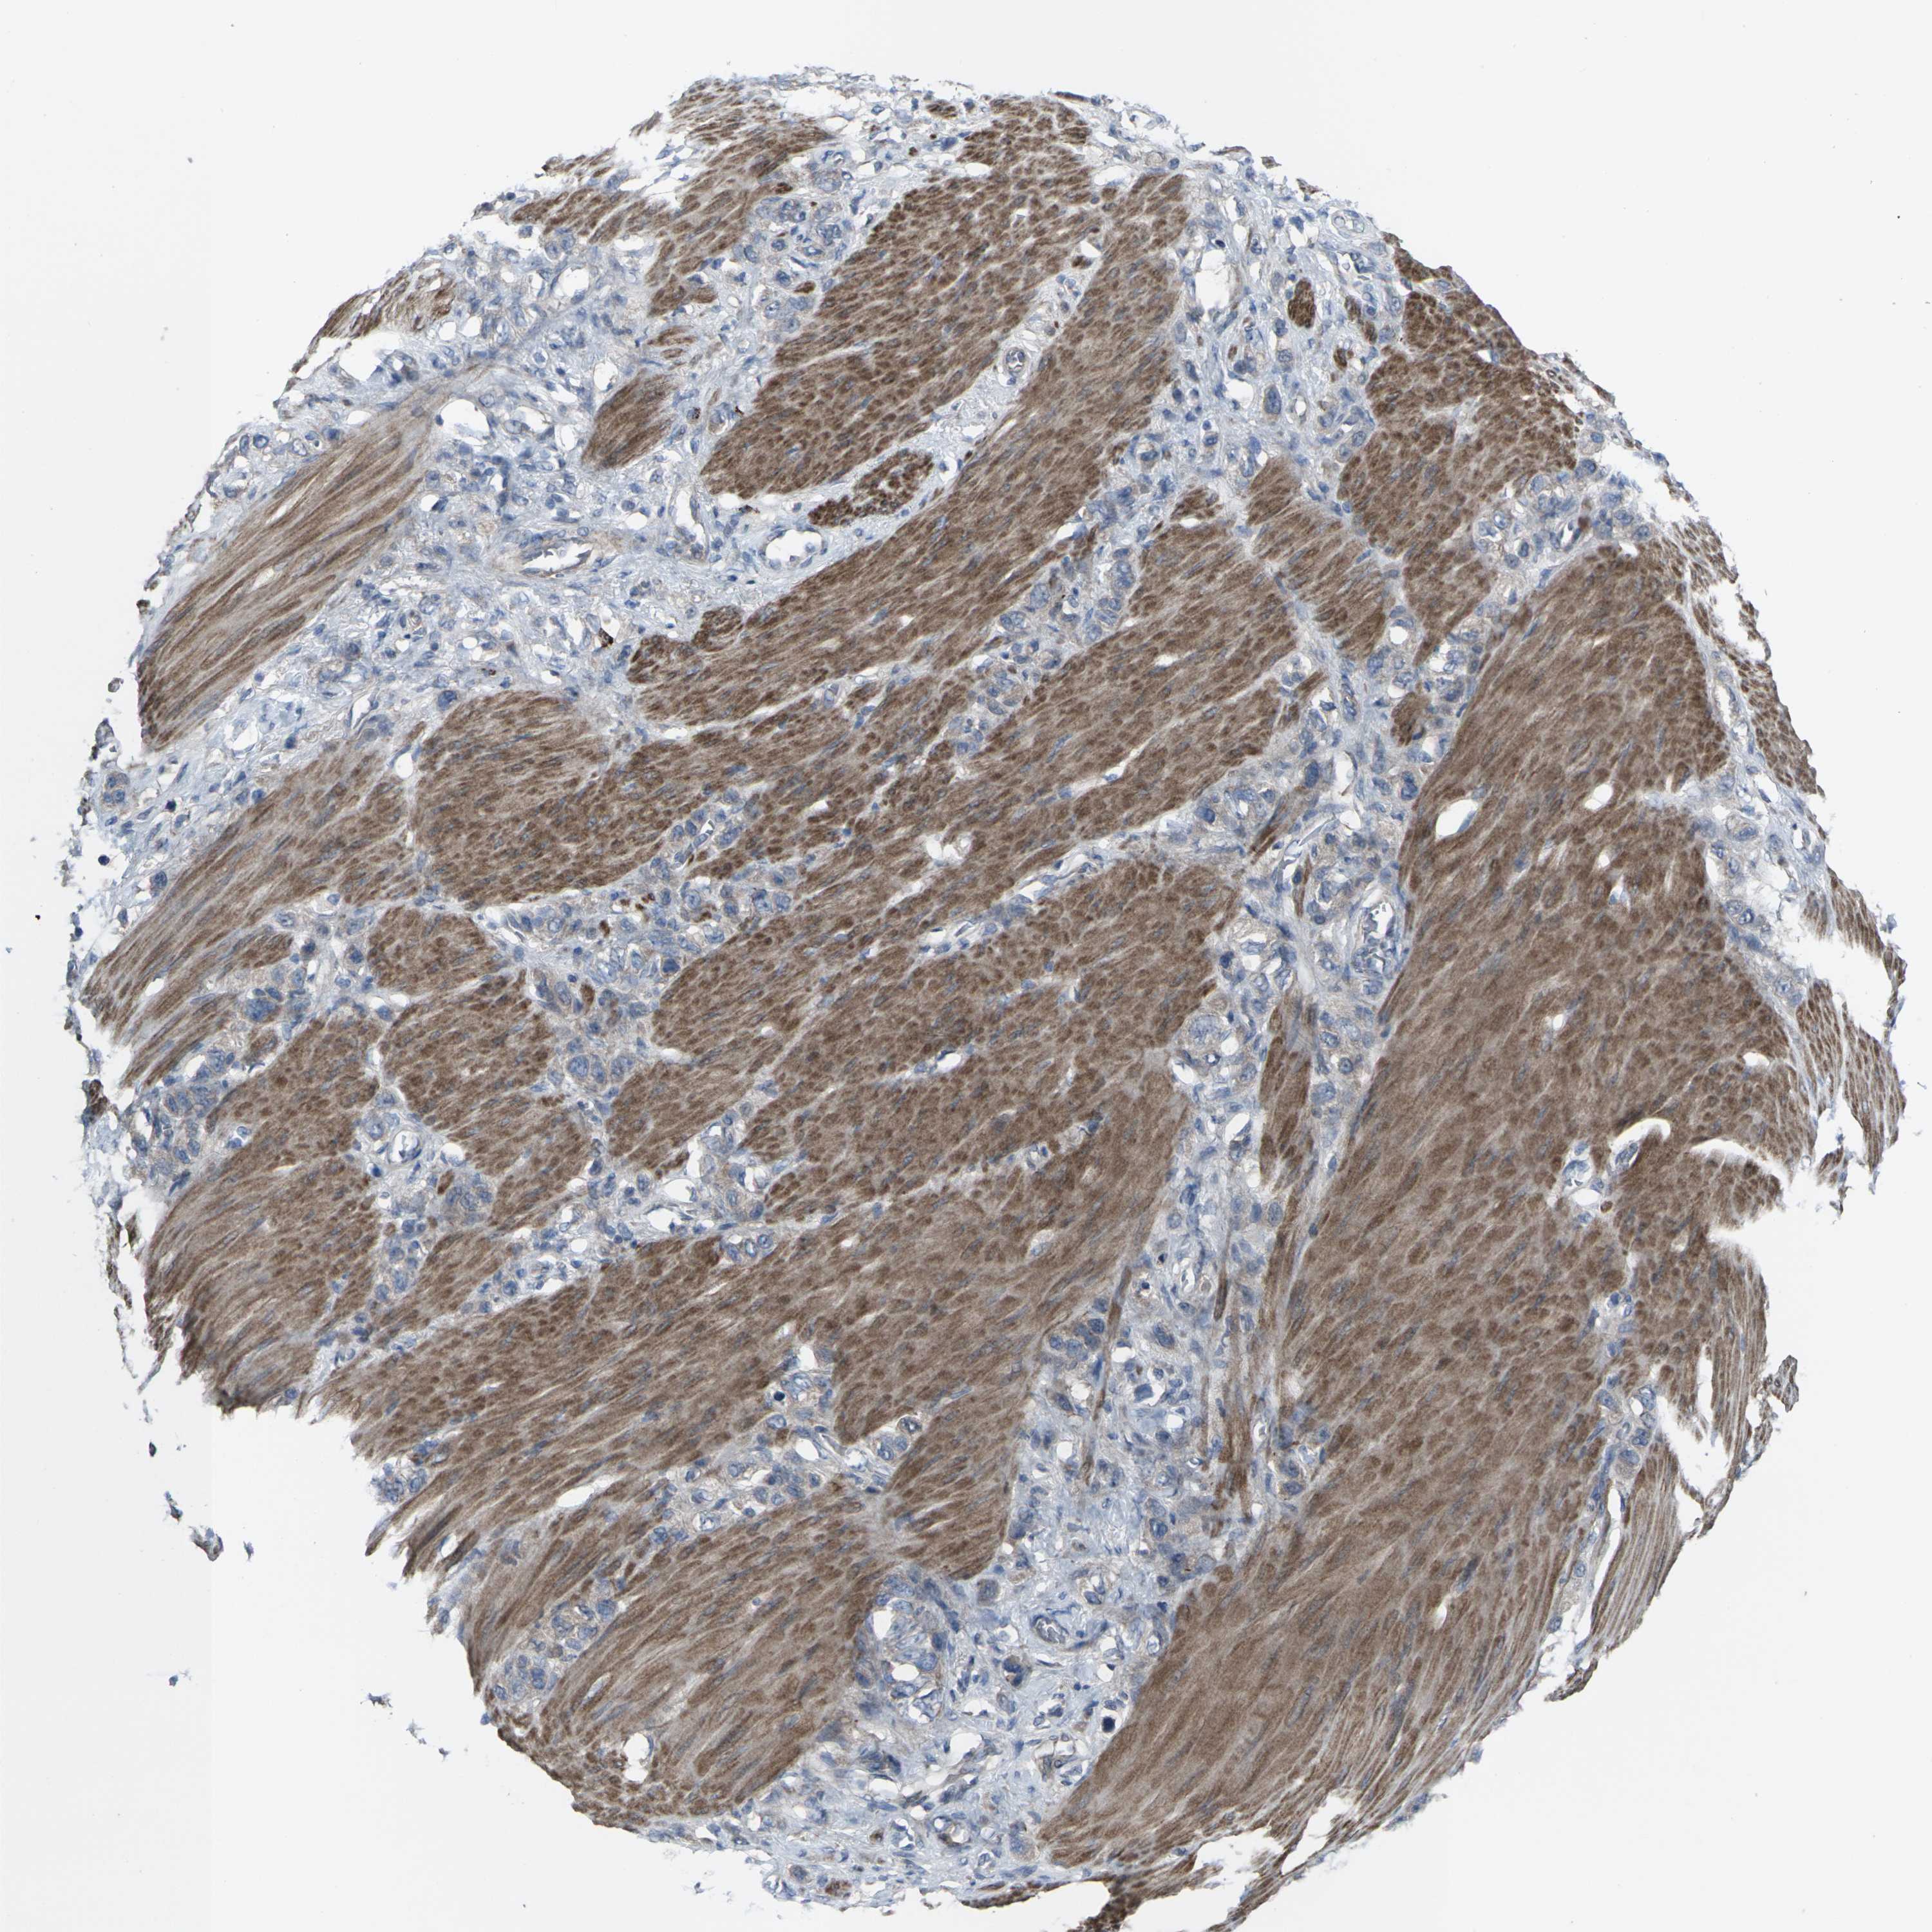

STOMACH CANCER - Protein expressioni

A mouse-over function shows sample information and annotation data. Click on an image to view it in a full screen mode. Samples can be filtered based on level of antibody staining by selecting one or several of the following categories: high, medium, low and not detected. The assay and annotation is described here.

Antibody stainingi

Antibody staining in the annotated cell types in the current human tissue is reported as not detected, low, medium, or high, based on conventional immunohistochemistry profiling in selected tissues. This score is based on the combination of the staining intensity and fraction of stained cells.

Each image is clickable and will lead to virtual microscopy that enables deeper exploration of all samples and also displays staining intensity scores, fraction scores and subcellular localization as well as patient and tissue information for each sample.

Antibody CAB011684

Staining

High

Medium

Low

Not detected

Intensity

Strong

Moderate

Weak

Negative

Quantity

>75%

75%-25%

<25%

None

Location

Nuclear

Cytoplasmic/membranous

Cytoplasmic/membranous,nuclear

Adenocarcinoma, NOS

Adenocarcinoma, High grade